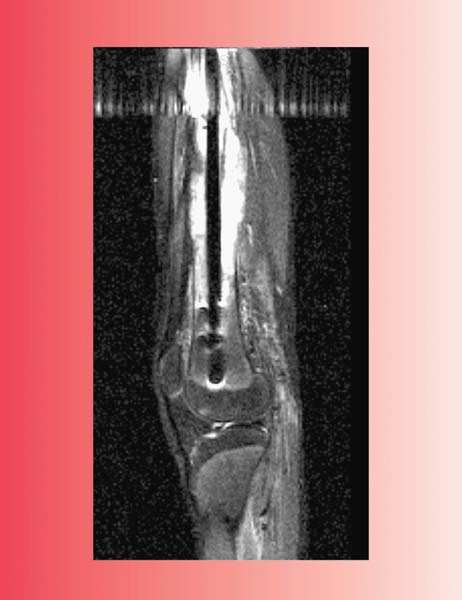

![]() |

|

▪ FIGURE 17-8 Codman’s triangle associated with an osteosarcoma of the distal femur in a teenager.

▪ FIGURE 17-9 The worst kind of trouble. This AP of the femur (A) and this lateral of the femur (B) show a pathologic fracture through a large destructive lesion. This AP (C) and lateral radiograph (D)

was taken after the surgeon treated the fracture with an intramedullary rod. The fracture did not heal and continued to show abnormal appearance. The patient was sent on for a consultation. (E,F) These MR images show the intramedullary rod passing through the malignancy in the distal femoral diaphysis. The entire shaft of the bone has been contaminated, compromising attempt at limb salvage surgery. |